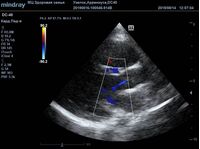

Найти их очень просто, достаточно сечений LAXLV (длинная ось) и SAXBASE (короткая ось). Специфические крупные шаровидные структуры – узелки Аррениуса - на кончиках полулуний клапана обнаружил ультразвуковой прибор Mindray DC-40. В цветовом допплере без труда определяется аортальная регургитация легкой степени. Оценить её можно в CFM по соотношению JW/LVOT.

Приборы среднего класса прекрасно справляются с этой задачей. Чтобы использовать возможности прибора на максимум необходимо уменьшить поле обзора (Front of view - FOV), тогда увеличится частота кадров и качество картинки при поиске мелких структур. Также частота кадров увеличивается при снижении уровня persistence, что актуально для детского возраста и высокой частоты сокращения сердца.